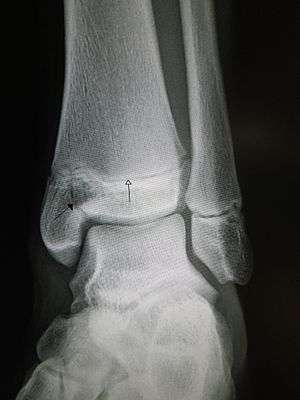

| |

| An X-ray of the left ankle showing a Salter–Harris type III fracture of medial malleolus. Black arrow demonstrates fracture line while the white arrow marks the growth plate. | |